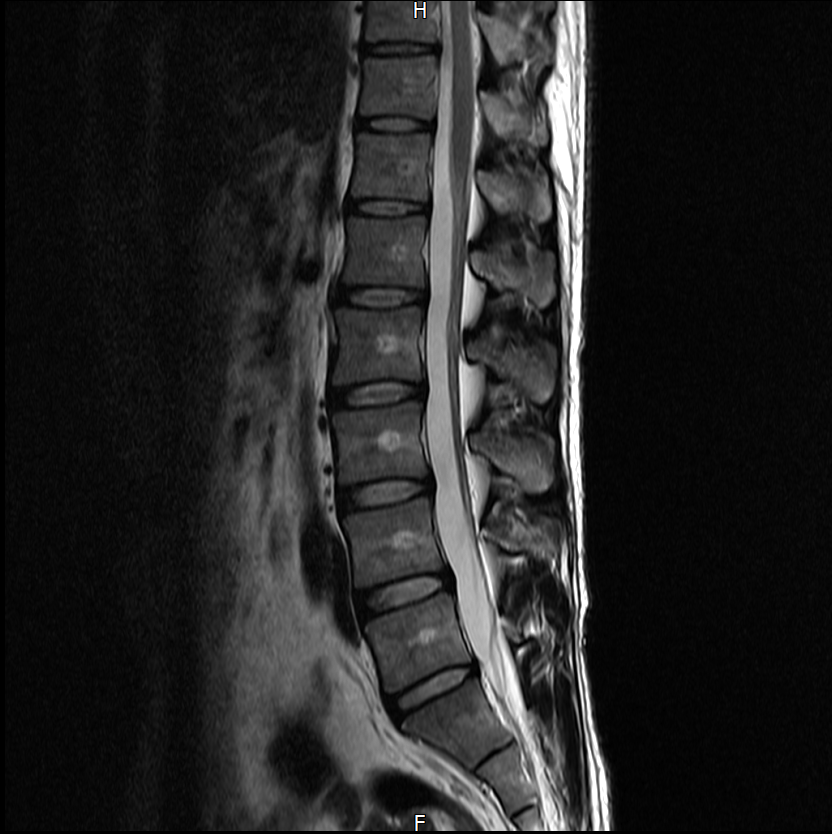

아래는 저의 경추과 요추 MRI 사진 첨부합니다.

※우리들병원 (신경외과 대표원장) : 경추,요추 MRI 촬영했고 요추는 매우 건강하고 경추에는 일자목에 퇴행성 디스크가 보이지만 한쪽팔에 저림이나 힘빠짐을 유발할 정도는 절대아니고, 다른 원인을 찾아야한다고 했습니다.

※분당서울대병원 재활의학과 : 근전도검사 이상없음, 경추 요추 MRI를 봐도 근골격계 문제로 보기 어렵다. 신경계 문제도 아니다.

3명이 디스크가 아니라고 하는데 1명이 디스크일수 있다고 하니까 조금 어렵습니다. 경추디스크가 약간은 있으니 팔저림은 설명할수 있다해도 다리저림은 설명이 안됩니다.. MRI 결과상 요추는 매우 건강하다고 하셨거든요.